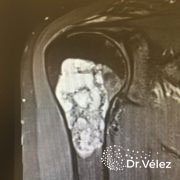

¿Qué es un tumor de células gigantes?

El tumor de células gigantes (TCG) son tumores poco comunes.

Suelen aparecer en diferentes localizaciones del cuerpo, pero suelen tener más incidencia en los extremos de los huesos largos y en la articulación de la rodilla.

Según la OMS (Organización Mundial de la Salud), está clasificado como una lesión agresiva y potencialmente maligna debido a su evolución impredecible. No obstante, el 80% de los casos tienen un curso benigno.

Dependiendo del grado de aparición histológico de las células estromales y el número de células gigantes y mitosis, los tumores de células gigantes se clasificaran como: Benignos, agresivos o malignos.

¿Cómo se diagnostica?

Para diagnosticarlo, su médico realizará una exploración física, y puede

solicitar las siguientes pruebas de imagen:

• Radiografías

• Tomografía computarizada (TAC)

• Resonancia magnética

• Gammagrafía ósea